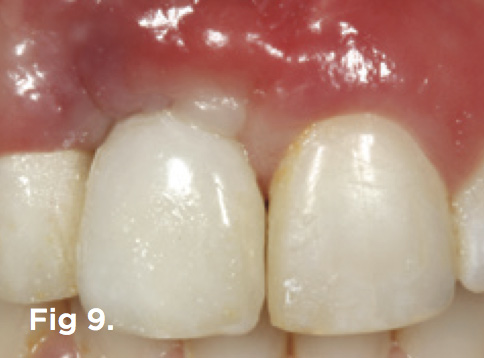

Fig 9. The mucosal tissue was nonsurgically sculpted with pressure through subgingival contour to the temporary restoration.

Figure 9

After 6 months of healing of the implant, stage 2 uncovering was performed and the mucosal tissues were allowed to mature for another 2 to 3 weeks. A temporary screw-retained implant cylinder was joined to the implant and acrylic crown (Figure 8). The subgingival shape of the temporary was modified with additional acrylic and the technique of non-surgical tissue sculpting, which was developed to provide the proper emergence profile to the mucosal tissues.27 It is important that the temporary blanching (ischemia) of the mucosal tissues dissipate after 10 minutes (Figure 9). After 3 weeks, soft-tissue scalloping through gingivectomy was done to recreate the proper shape (ie, gingival zenith)28 and proportion for the mucosal tissues (Figure 10). Fiberotomy on the distal aspect of tooth No. 7 was not performed during treatment; therefore, this papilla was slightly more incisal (longer) than the adjacent papillae (Figure 11). A final impression was made of crown No. 7 and implant No. 8 at the implant level to enable a working cast to be made in the laboratory. An all-ceramic custom abutment was made for implant No. 8, and splinted full-coverage units were made for crowns No. 7 and No. 829 (Figure 12). The custom abutment was seated intraorally and torqued according to the manufacturer’s recommendation. The crowns were luted with provisional cement and maintained at 4-month recall intervals (Figure 13). Note the health of the periodontal tissues and its integration with the adjacent teeth and surrounding gingiva, taking a complex esthetic and functional problem for a patient with a high smile line and providing a predictable restorative and esthetic outcome (Figure 14).